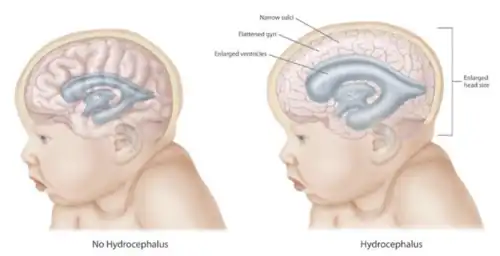

Hydrocephalus is a condition in which cerebrospinal fluid (CSF) builds up within the brain, which can cause pressure to increase in the skull.[4] Symptoms may vary according to age. Headaches and double vision are common. Elderly adults with normal pressure hydrocephalus (NPH) may have poor balance, difficulty controlling urination or mental impairment.[4] In babies, there may be a rapid increase in head size. Other symptoms may include vomiting, sleepiness, seizures, and downward pointing of the eyes.[1]

Hydrocephalus is difficult to detect clinically before delivery, although enlarged ventricles can be spotted on ultrasonography as early as 18–20 weeks gestation.[7] Since infants' skulls are not fully fused together at the cranial sutures yet, they have soft spots on their skulls known as open fontanelles.[8] This anatomic characteristic means that infants' skulls can visibly grow in size when cerebrospinal fluid accumulates. Therefore, infants with hydrocephalus may present with an enlarged skull (or rapid growth in skull size), bulging fontanelles, or separated cranial sutures.[8][9] Parents or physicians may also note that the infant is more irritable or tired than normal. Other symptoms include seizures, inability to look upwards ("sunset eyes" or "setting sun" sign), and pauses in breathing.[8][9] Infants may also present with lack of weight gain or failure to meet motor and developmental milestones.[10] Imaging can be done to confirm the suspected diagnosis of hydrocephalus. In infants, the open fontanelles allow for use of head ultrasonography. This allows pediatricians to minimize radiation exposure and come up with a diagnosis quickly.[8] If further information is needed, an MRI can be done.[7]

Mechanism of symptoms

When the cerebrospinal fluid builds up, it causes compression of the brain, which leads to the symptoms of convulsions, intellectual disability, and epileptic seizures. These signs occur sooner in adults because their skulls are no longer able to expand to based on the increasing fluid volume. Fetuses, infants, and young children with hydrocephalus have head enlargement, excluding the face, because the pressure of the fluid causes the individual skull bones—which have yet to fuse—to bulge outward at their juncture points.[39]

CSF can accumulate within the ventricles, a condition called internal hydrocephalus. It may result in increased CSF pressure. The production of CSF continues, even when the passages that normally allow it to exit the brain are blocked. Consequently, fluid builds inside the brain, causing pressure that dilates the ventricles and compresses the nervous tissue. Compression of the nervous tissue usually results in irreversible brain damage. If the skull bones are not completely ossified when the hydrocephalus occurs, the pressure may also severely enlarge the head. The cerebral aqueduct may be blocked at the time of birth or may become blocked later in life because of a tumor growing in the brainstem.[43]